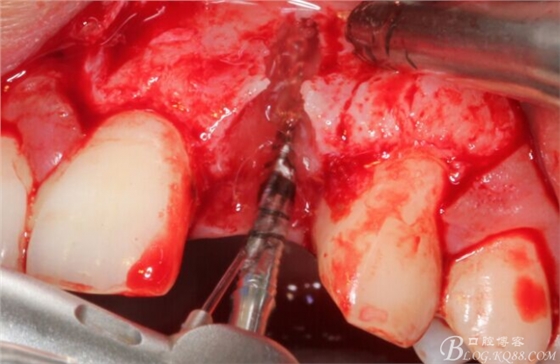

于是我果斷告知患者,手術(shù)失敗了,不能拖延,如不及時(shí)處理,炎癥繼續(xù)發(fā)展會(huì)很快波及鄰牙牙槽骨。患者接受我的建議。切開翻瓣,骨粉及生物膜消失了,骨吸收嚴(yán)重,幸運(yùn)的是,因?yàn)樘幚砑皶r(shí),鄰牙骨支持依然存在。

徹底掻刮。